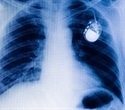

A pacemaker is a small battery-operated electronic device placed in your body, usually by surgery, to help stabilize and regulate abnormal heart rhythms to a more regular pattern. A temporary pacemaker helps a recovering heart to manage a slow heartbeat (bradycardia) after a heart attack. In these cases, the pacemaker may be attached to the clothes rather than implanted under the skin. Permanent pacemakers are implanted in patients with chronic heart failure or a slow or irregular heartbeat.

The pacemaker is implanted underneath the chest skin just below the collar bone and connected to the heart with tiny wires. The whole procedure takes around an hour to complete.

The two main components of a pacemaker include a pulse generator and connecting leads (electrodes). The former is a small metal container housing a battery and the electrical circuitry that controls the rate of electrical pulses sent to the heart. The computerized electrical circuit converts any generated energy into electrical impulses that travel via the wires to the heart.

The electrodes, one to three in number, are placed in one or more chambers of the heart to deliver the electrical pulses to adjust the heart rate. Modern leadless pacemakers, however, are implanted directly into the heart muscle. Chest radiography helps doctors identify the pacemaker and the lead type, the lead course within the heart, and the type of lead fixation to the myocardium. The pacemaker leads have a lifespan of approximately eight to 10 years.

All modern pacemakers use complementary metal oxide semiconductor (CMOS) technology. CMOS technology uses only some random-access memory (RAM) to store diagnostics and history and a few kilobytes of read-only memory (ROM) containing the program. All the components are housed within a titanium case with a connector block to attach the leads. The outer casing is generally laser etched with manufacturing and model details. Some models also include radio-opaque symbols of a characteristic shape so that an X-ray image identifies the device.